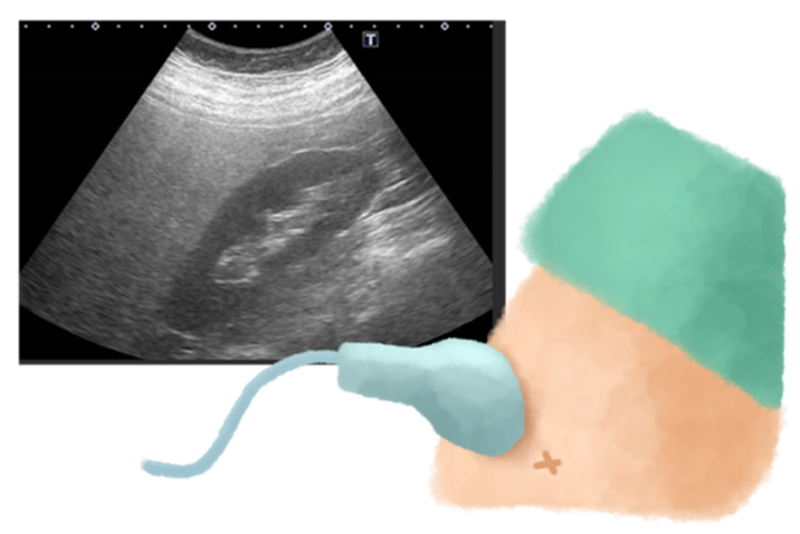

肝臓病専門医のもとでは、まず血液検査で肝機能の数値(AST, ALT, γ-GTPなど)を確認し、腹部超音波(エコー)検査を行います。エコー検査は、体に負担をかけることなく、肝臓の形や脂肪の蓄積具合、そして腫瘍の有無などをリアルタイムで詳細に観察できる非常に有用な検査です。